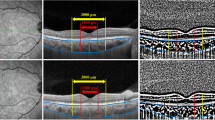

In the CPRP group, 1200–1600 laser burns with spot size of 200 µm, duration of 200 ms and spacing of 0.5 burn width were applied. Treatment started from the vascular arcade toward the periphery (Fig. 1). In the ETRP group, the entire retina anterior to the equator as well as the capillary non-perfusion areas between the vascular arcade and the equator were treated using the same spot size, spot duration and spacing between laser spots (Fig. 2). One of the authors specified the capillary non-perfusion areas on the angiograms. In order to ensure covering the entire ischemic areas as well as their margins, which usually have a high density of microaneurysms, the laser applied 1-disk diameter beyond the ischemic areas. The equator was localized in relation to the vortex ampulla.

As shown in Table 1, the difference of baseline CMT was insignificant between the groups: 245 ± 26 vs. 248 ± 28 µm in the ETRP and CPRP groups, respectively (P = 0.36). Three months following laser, mean CMT increased to 285 ± 40 and 281 ± 44 µm in the ETRP and CPRP groups, respectively (Table 2). Although these changes were significant in both arms (41.08 µm in the ETRP group, 95% CI 33.52–48.64, P < 0.001 and 33.31 µm in the CPRP group, 95% CI 24.90–41.72, P < 0.001), the difference between the groups was not significant (P = 0.26). Furthermore, the changes of VA (logMAR) and CMT were found to be correlated positively among patients (r = 0.165, P = 008). However, eyes with worsened BCVA had greater increase in CMT (mean increase difference 23 µm, 95% CI 12–36, P < 0.001) compared to the eyes with stable or improved BCVA.

Present study demonstrated that mean CMT increased in both ETRP and CPRP groups (41 and 33 µm, respectively) which was almost similar. Central macular thickening after laser therapy has been shown in numerous other studies [29–31]. McDonald and Schatz [25] reported increased macular edema in 43% of their cases, occurred 6–10 weeks after PRP. Soman et al. [30] reported 15% increase in CMT after PRP in eyes with PDR without clinically significant macular edema. We found 18 and 15% CMT rise in the ETRP and CPRP groups, respectively. Additionally, type of macular edema based on OCT findings has been shown to be more relevant and better correlated with visual outcome than the quantitative estimation of foveal thickness [30].